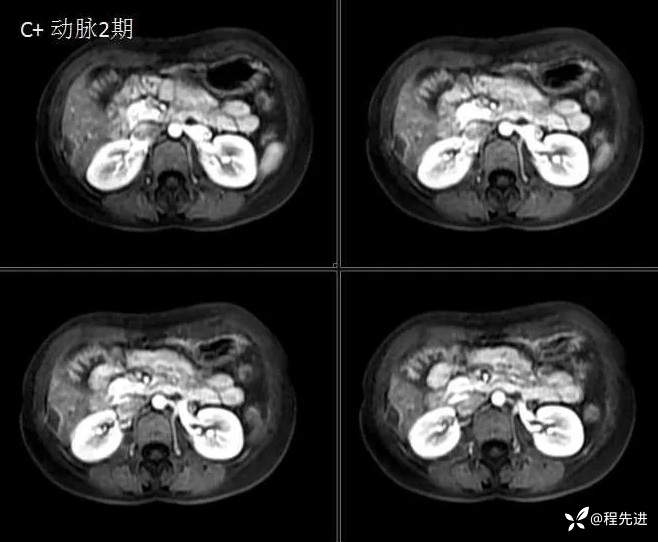

MRI检查: